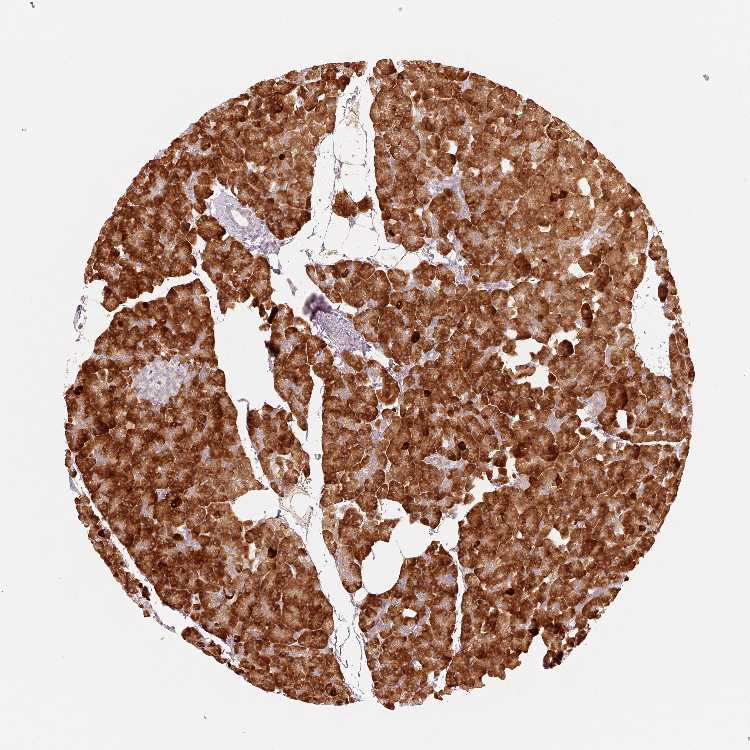

OR13C3